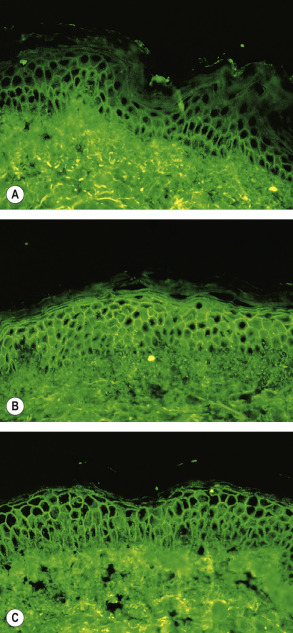

The sites of blisters in pemphigus vulgaris and foliaceus are explained logically by the desmoglein compensation theory: Dsg1 and Dsg3 compensate for each other when they are coexpressed in the same cell ( Fig. 29.4 ) . While patients with pemphigus foliaceus have only anti-Dsg1 IgG autoantibodies, individuals with the mucosal-dominant type of pemphigus vulgaris have only anti-Dsg3 IgG autoantibodies. Those with the mucocutaneous type of pemphigus vulgaris have both anti-Dsg3 and anti-Dsg1 IgG autoantibodies . Of note, the intraepithelial expression pattern of Dsg1 and Dsg3 differs between the skin and mucous membranes. In the skin, Dsg1 is expressed throughout the epidermis, but more intensely in the superficial layers (see Fig. 29.1C ), whereas Dsg3 is expressed in the lower portion of the epidermis, primarily in the basal and parabasal layers (see Fig. 29.1A ). In contrast to the skin, Dsg1 and Dsg3 are expressed throughout the squamous layer of mucosa, but Dsg1 is expressed at a much lower level than Dsg3 (see Fig. 29.4B ) .